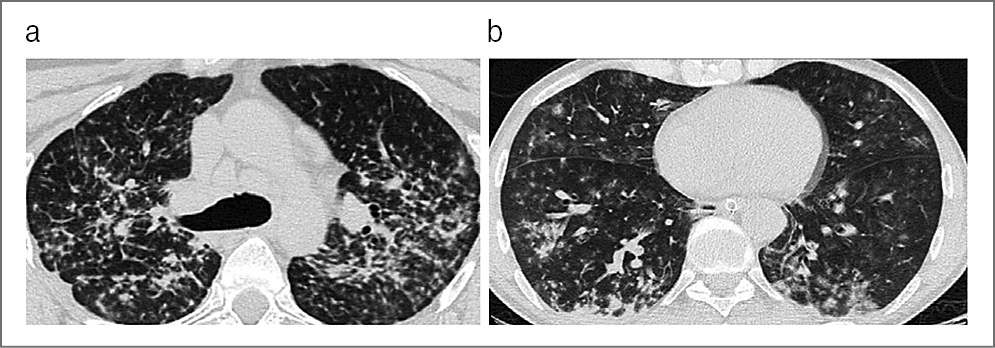

В качестве примеров приводим КТ органов грудной клетки, иллюстрирующую сходство КТ-признаков у больных 1 и 2-й групп, с этиологической верификацией бактериальной пневмонии (вызванной S. aureus) с COVID-19 (рис. 1, а) и без COVID-19 (рис. 1, b); микобактериозом легких (обусловленным M. avium complex) с COVID-19 (рис. 2, а) и без COVID-19 (рис. 2, b); пневмоцистной пневмонией (вызванной P. jiroveci) с COVID-19, ТОД (рис. 3, а) и без COVID-19 (рис. 3, b) и вирусной пневмонией (вследствие инфекции Cytomegalovirus hominis) с COVID-19, ТОД (рис. 4, а) и без COVID-19 (рис. 4, b).

Рис. 3. КТ органов грудной клетки. Аксиальная проекция, режим легочного окна: а – пациент, 29 лет, с 4B-стадией ВИЧ- инфекции в фазе прогрессирования, без АРВТ и верифицированной коинфекции COVID-19, ТОД и пневмоцистной пневмонией (вызванной P. jiroveci); b – пациент, 30 лет, с 4B-стадией ВИЧ- инфекции в фазе прогрессирования, без АРВТ и верифицированной коинфекции ТОД и пневмоцистной пневмонией (вызванной P. jiroveci).